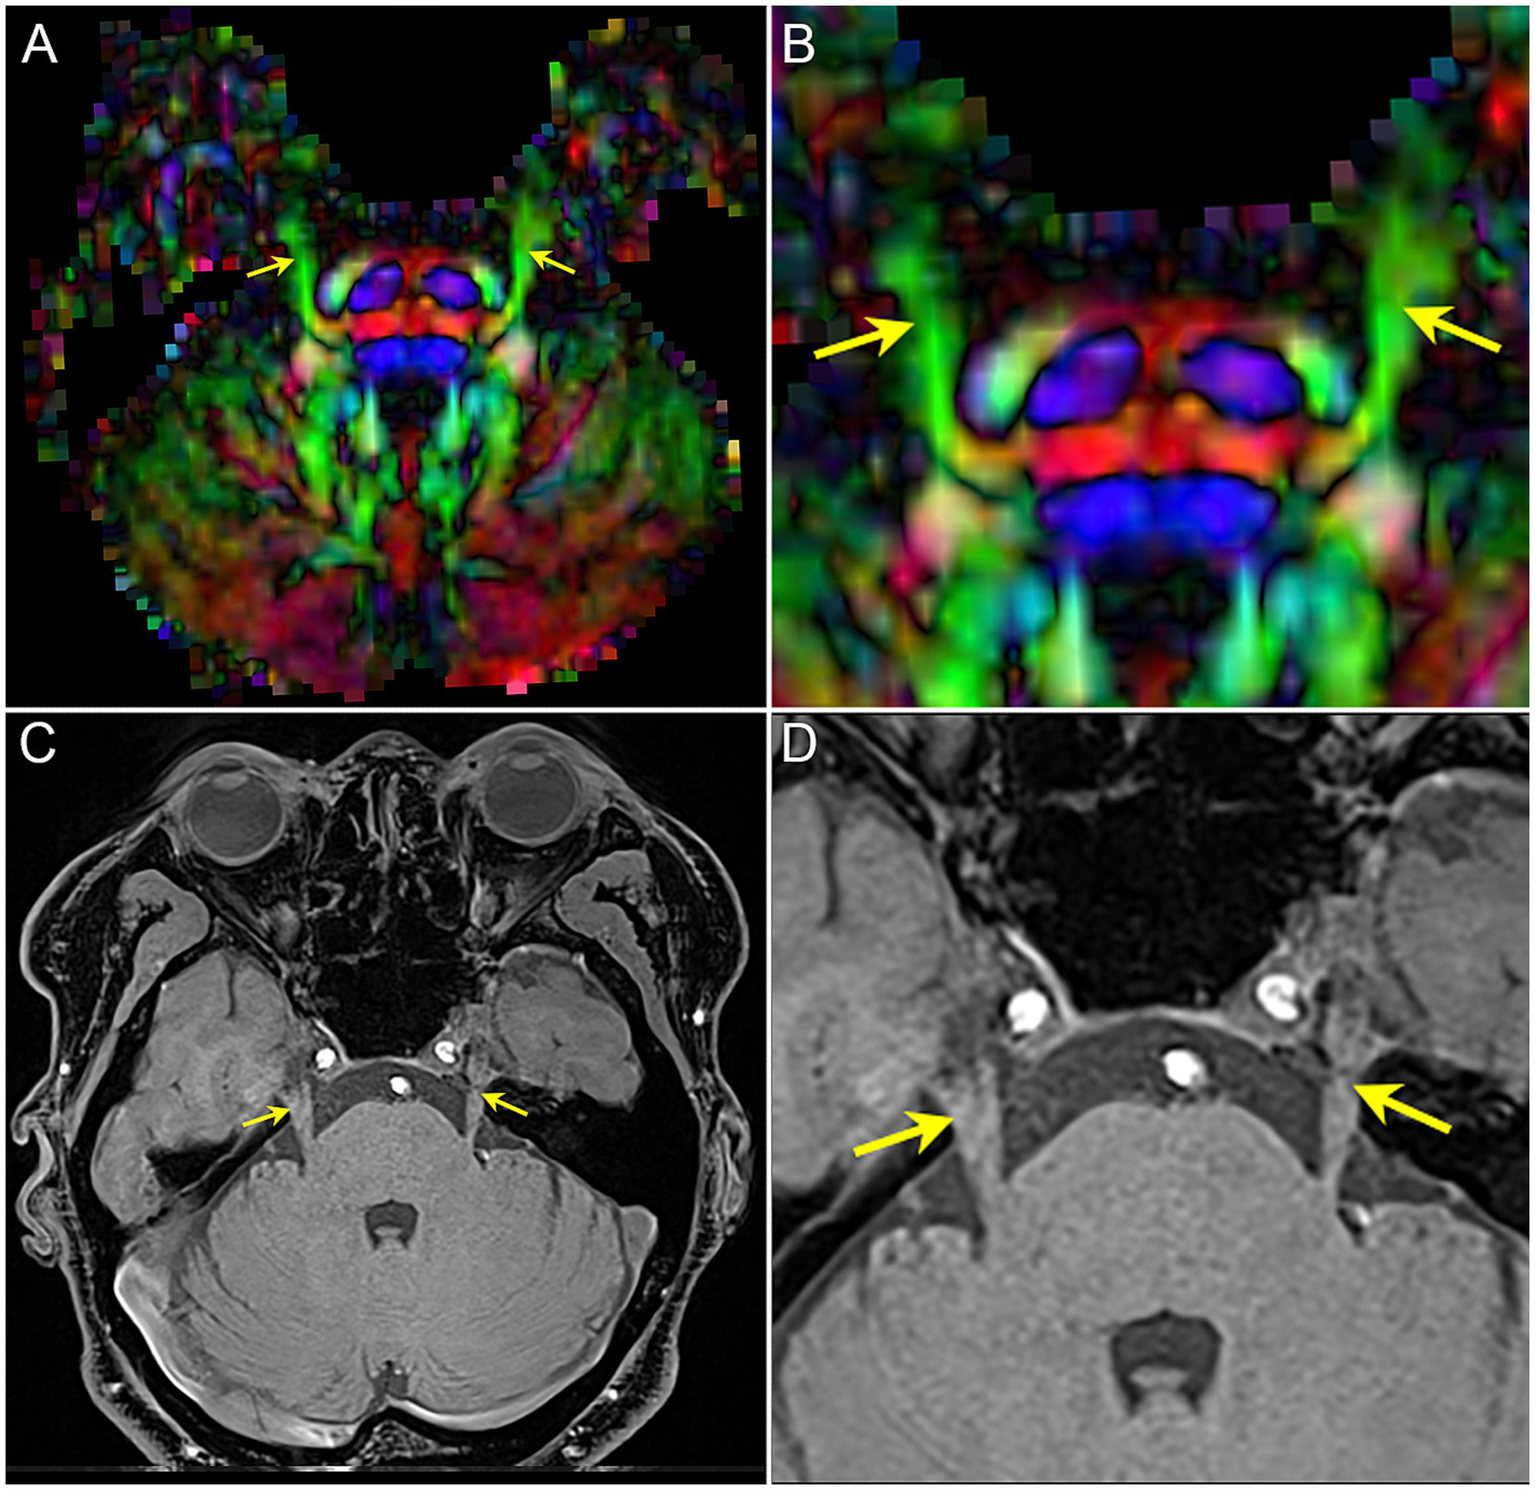

Figure 2

The image shows the bilateral CNV tracts in DTI and anatomical MRI. (A,B) the FA map of DTI image, image B is the focal magnification of (A); (C,D) T1-weighted image of MRI, image D is the focal magnification of (C). Yellow arrow: the bilateral CNV.

By three-dimensions images of DTI and MRI anatomical imaging, we identify the trigeminal ganglion area on the FA map (Figure 2). The TG is crescent-shaped, and the width of TG on axial position is between 3.58 and 8.19 mm (31–34). We selected 4 slicers (thickness 2.00 mm) to measure diffusivity metrics. Then, the FA values of the two-side TG are extracted from four consecutive slices on the coronal view of the FA map including the CNV tract. Regions of interest (ROI) were independently mapped in the same way by two trained personnel and subsequently confirmed by comparison to show reliability and avoid individual differences (35).